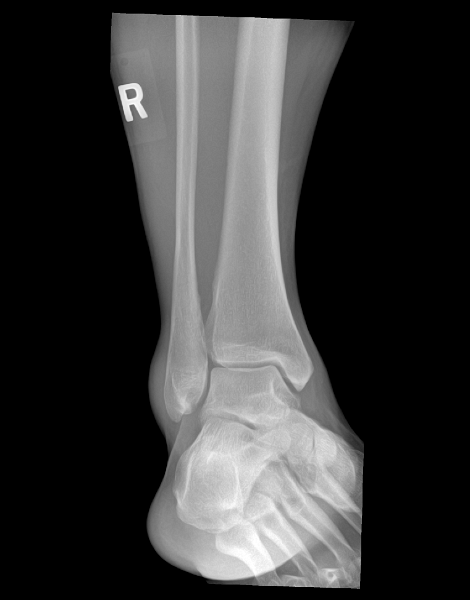

Ankle (1) Ankle (1) Ankle (2) Ankle (2) Ankle (3) Ankle (3)